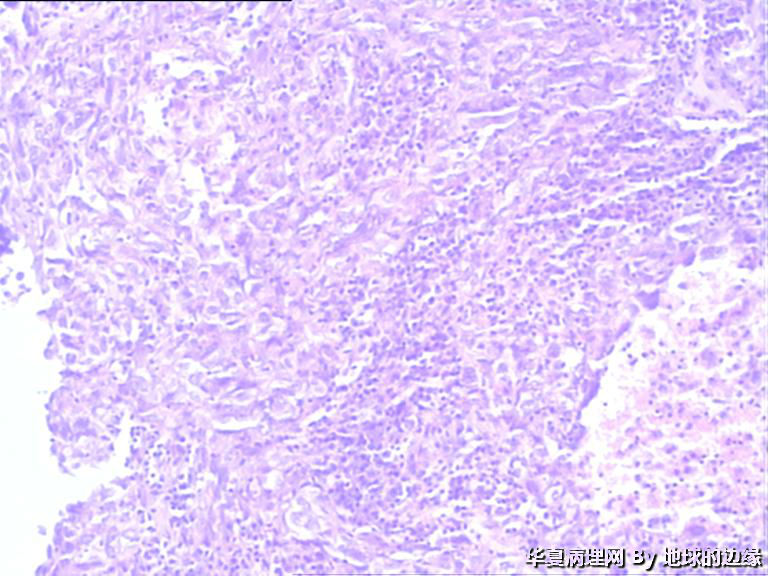

右肱骨肿瘤待查

病人女性,48岁

MRI示:右肱骨肿瘤待排,包块大小为10x8cm,活动度差,边界欠清,鱼肉组织(白色),肿块侵犯至骨外    组  织。

恶性。是转移还是原发,是骨肉瘤还是浆母?需要进一步资料并标记。

考虑肉瘤,转移癌也排除一下吧

目前Vimentin阳性,P53阳性,AFP,EMA,CK7,CK20,E-ca,CR,PLAP,CD99,ER,PR,CEA,均阴性,只是没做淋巴瘤这一套了